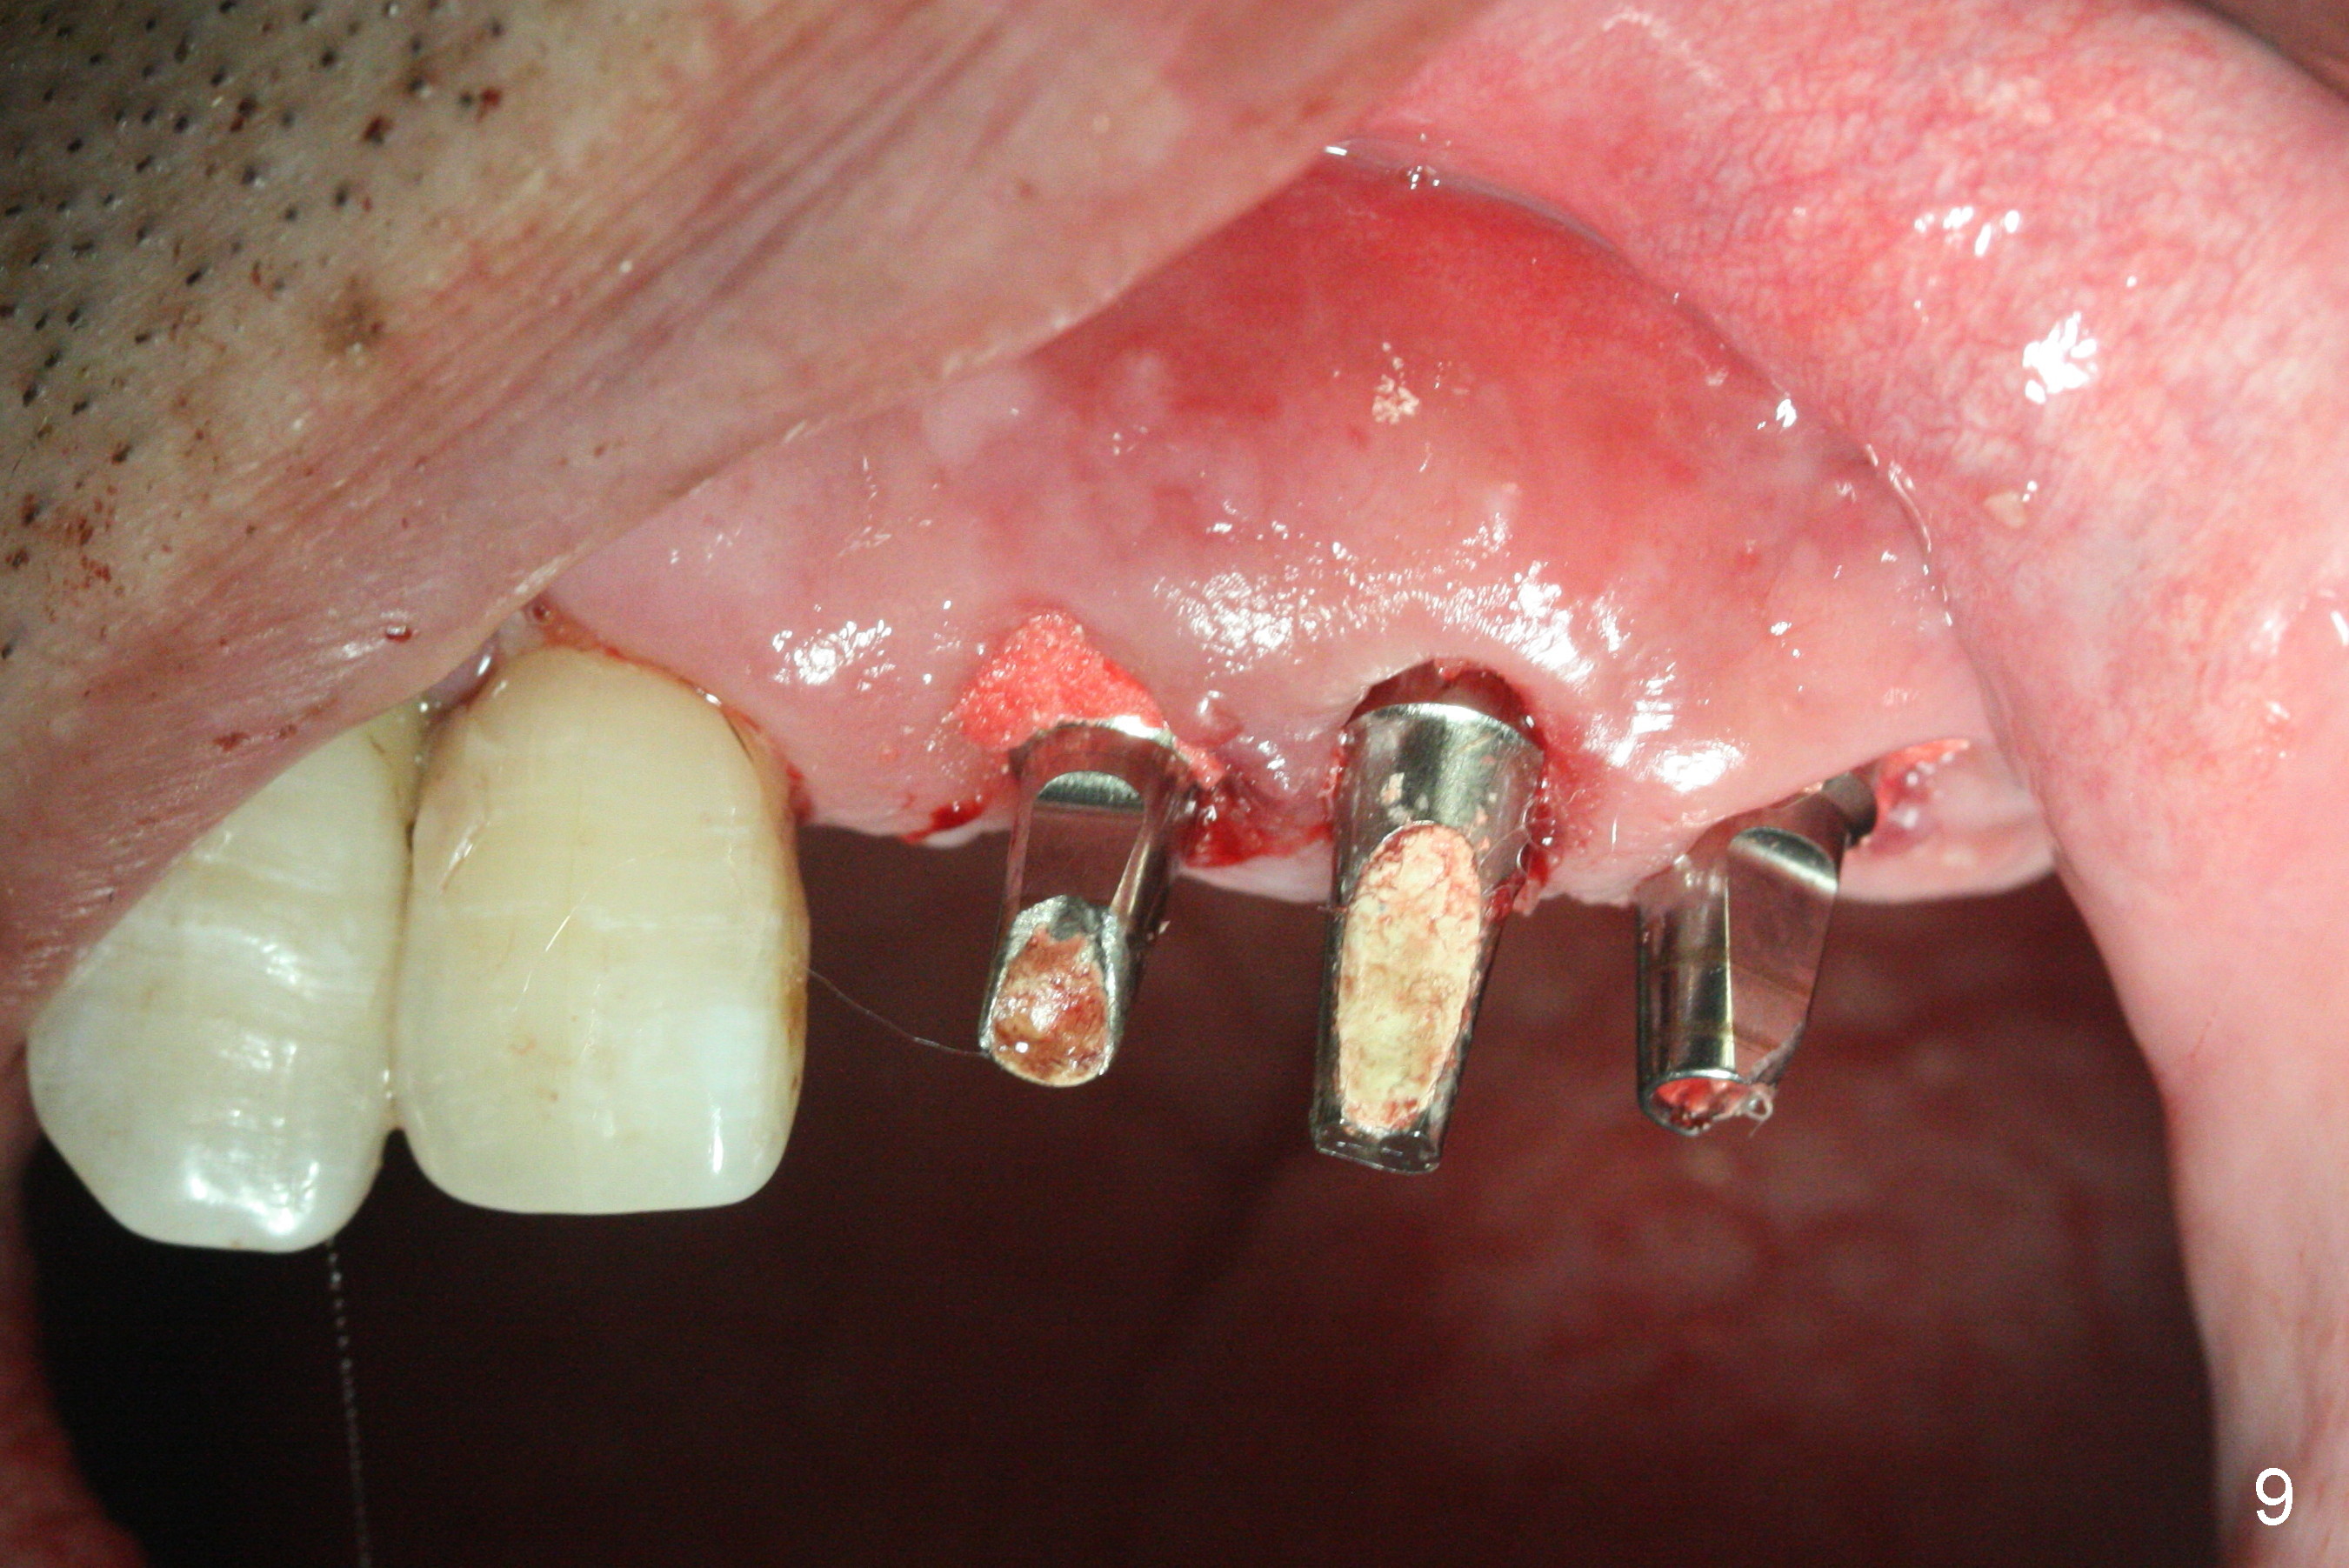

The dentition is poor except #6 and 8 (Fig.1). The gingiva is erythematous at #9-11 (Fig.2). The teeth #9 and 10 are extracted first; a 4x16 mm UF implant is placed at #9, while a 2 mm pilot drill is at the site of #10 (Fig.3). The implant at #9 is placed deeper with placement of 4.5x5.5(5) mm abutment; a 3.8x15 mm implant is placed at #10 initially (Fig.4). While the latter is placed deeper, a 4x16 mm implant is placed at #11 (Fig.5 after removal of #11-15 FPD (fixed partial denture)). In fact the trajectory at #11 is not difficult to be changed with 2 mm drill (Fig.6). After use of 3 mm drill, the implant is reinserted at #11 with ideal trajectory (Fig.7). After further seating of the implant at #11, graft is placed in the remaining sockets of #9-11 (Fig.8 *; later more graft is placed mesial to #11 implant (^)). Finally, a 4.5x7(5), 4.5x15° B (4) and 5.5x7(5) mm abutments are tightened and prepared (Fig.9) for splinted provisional at #9-10.